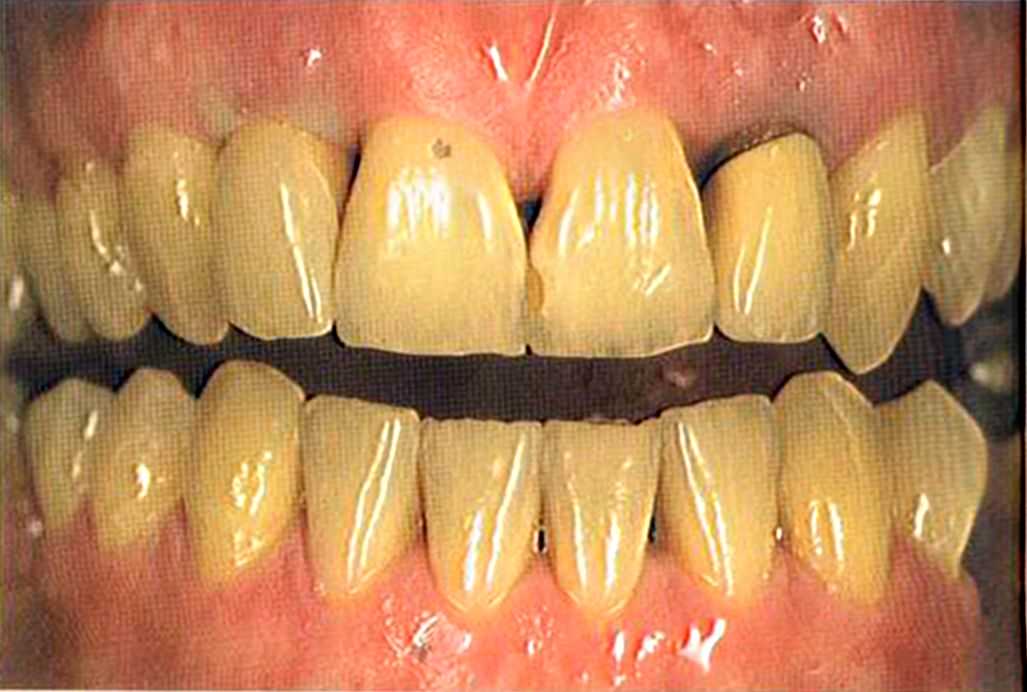

Вспомним, как все начиналось.

Первое лечение проходию много лет назад у другого доктора. Со временем ос те пи / ка уху дин ьась, особенно в пришеечной области. Этот пациент хотел новые коронки в области 12 и 22, по сомневсься, нас кол ько хорошо они будут выглядеть.

Фото внизу.

Результат с использованием In-Ceram развеял все сомнения, и решение об изготовлении коронки на другой боковой резец не заставило себя долго ждать.

После того как мы определит цвет зуба, решено быо сначсьа изготовить одну коронку.